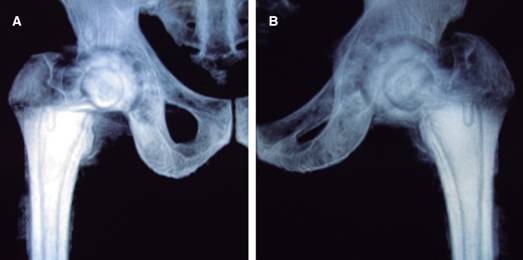

Figura 3: Imágenes tomográficas en vista anterior (A) y posterior (B) de articulación coxofemoral con prótesis total de cadera derecha en masculino de 78 años con calcificación de músculos periarticulares.